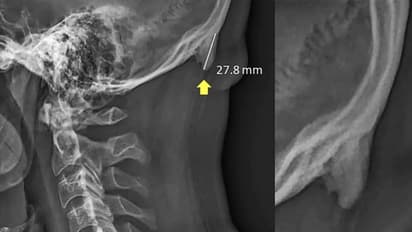

ಕ್ವೀನ್ಸ್ಲ್ಯಾಂಡ್ನಲ್ಲಿ 1200 ಎಕ್ಸ್-ರೇಗಳನ್ನು ಪರಿಶೀಲಿಸಿ ಅಧ್ಯಯನ ನಡೆಸಿದಾಗ ಈ ಆತಂಕಕಾರಿ ವಿಷಯ ಬೆಳಕಿಗೆ ಬಂದಿದೆ. 1200ರ ಪೈಕಿ ಮೂರನೇ ಒಂದು ಅಂದರೆ 400 ಎಕ್ಸ್-ರೇಗಳಲ್ಲಿ ತಲೆಯಲ್ಲಿ ಮೂಳೆಯಂತಹ ಹೆಚ್ಚುವರಿ ರಚನೆ ಕಂಡುಬಂದಿದೆ. ವಯಸ್ಸಾದವರಲ್ಲಿ ಇದು ಕಡಿಮೆ ಇದೆ. ಯುವಜನರಲ್ಲಿ ಹೆಚ್ಚಿನ ಪ್ರಮಾಣದಲ್ಲಿ ಕಾಣಿಸುತ್ತಿದೆ ಎಂದು ವರದಿಗಳು ತಿಳಿಸಿವೆ.

ಮೊಬೈಲ್ ಫೋನ್ ಅನ್ನೇ ದಿಟ್ಟಿಸುತ್ತಾ ಯುವಜನತೆ ಕೂರುವುದರಿಂದ ತಲೆಯ ಮೇಲಿನ ಭಾರ ಬೆನ್ನುಮೂಳೆಯ ಮೇಲೆ ಬೀಳುತ್ತಿಲ್ಲ. ಬದಲಾಗಿ ತಲೆಯ ಹಿಂಭಾಗದಲ್ಲಿನ ಮಾಂಸಖಂಡಗಳಿಗೆ ವರ್ಗಾವಣೆಯಾಗುತ್ತಿದೆ. ಹೀಗಾಗಿ ಅಲ್ಲಿ ಸ್ನಾಯುತಂತು (ಟೆಂಡನ್) ಹಾಗೂ ಮೂಳೆಕಟ್ಟು (ಲಿಗಮೆಂಟ್)ಗಳನ್ನು ಮೂಳೆ ಸೃಷ್ಟಿಮಾಡುತ್ತಿದೆ. ಹೀಗಾಗಿ ತಲೆಬುರುಡೆಯ ಕೆಳಭಾಗದಲ್ಲಿ ಕೋಡು ಬೆಳೆಯುತ್ತಿದೆ.